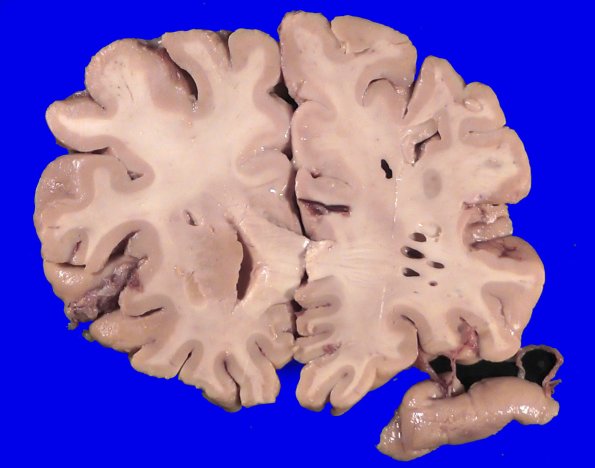

Washington University Experience | BASIC PROCESSES | Artifacts | Artifact - Swiss Cheese Brain | 34A3 Swiss Cheese Brain (Case 12) Gross _3

A typical swiss cheese artifact predominantly involves white matter whose long axis of the lozenge shaped cavity typically parallels the direction of white matter tracts.